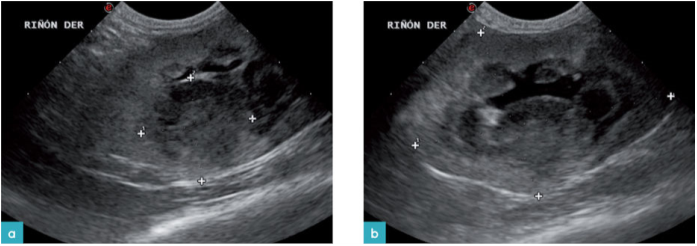

在健康猫和那些患有不同肾脏疾病或阻塞患猫中会出现肾盂的扩张。曾有报道具有临床正常肾功能的猫,其肾盂发生1.6mm的扩张; 且该扩张会随着肾功能损伤,肾盂肾炎和梗阻等症状逐渐增加。术语“肾盂扩张”用于描述肾盂轻度至中度,非阻塞性扩张,其中静脉内补液,利尿剂,伴随多尿的肾损伤,肾盂肾炎,终末期肾病和肾移植都可能继发肾盂扩张(图26)。

在具有阻塞问题的猫中,尽管肾盂直径较小,但肾盂扩张的倾向比其他情况 (其测量高达13mm) 时要严重(表2.图2-8)。通常通过肾积水来识别肾盂扩张的程度。随着扩张的增加,皮质变得越来越萎缩,在最严重的情况下,我们可以观察到一个非常薄的皮质围绕着一个大的液体填充腔,而当强回声线垂直于皮质时则表明出现了肾盂憩室(图29.视频14)。在输尿管狭窄的情况下,肾盂扩张平均达11.75 mm。